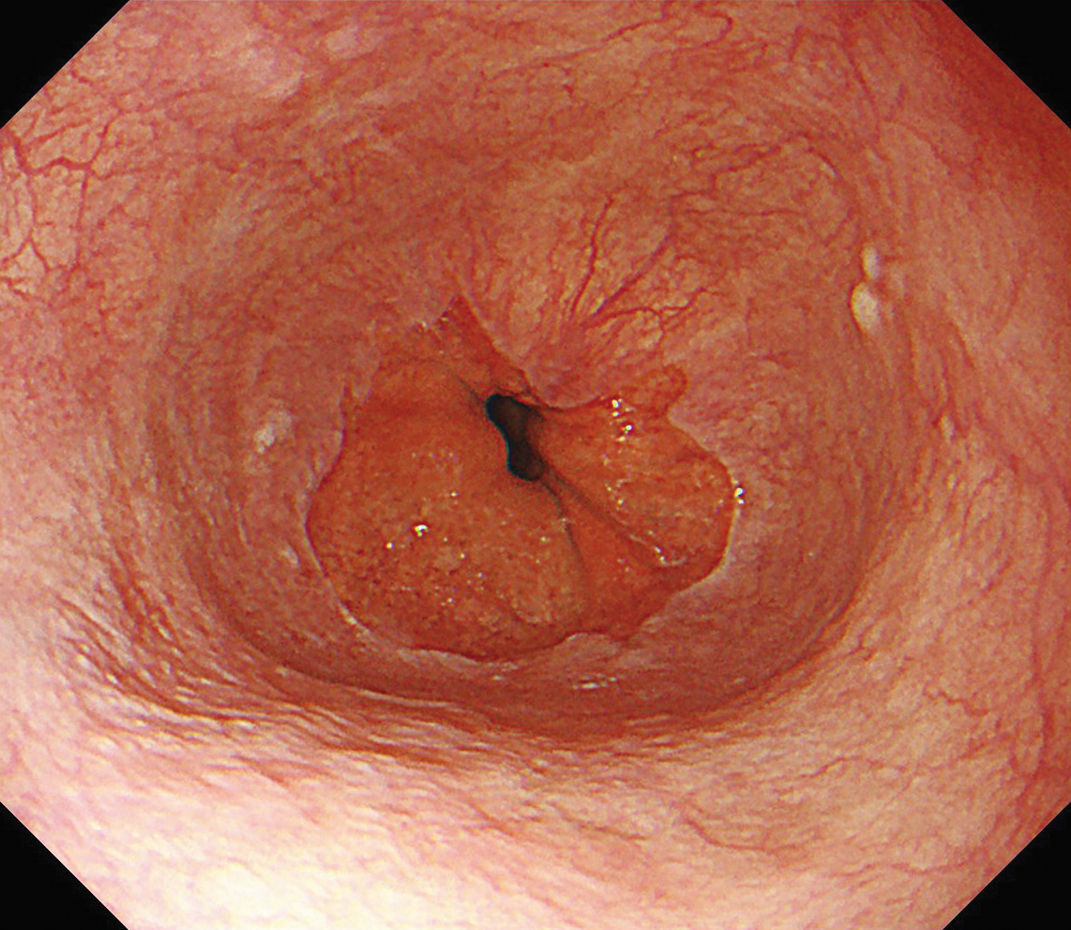

EVIS X1×GIF-1200N 症例画像

胃体部 見上げ観察 胃潰瘍症例

1視野で体下部から噴門部まで明るい視野での観察に貢献する